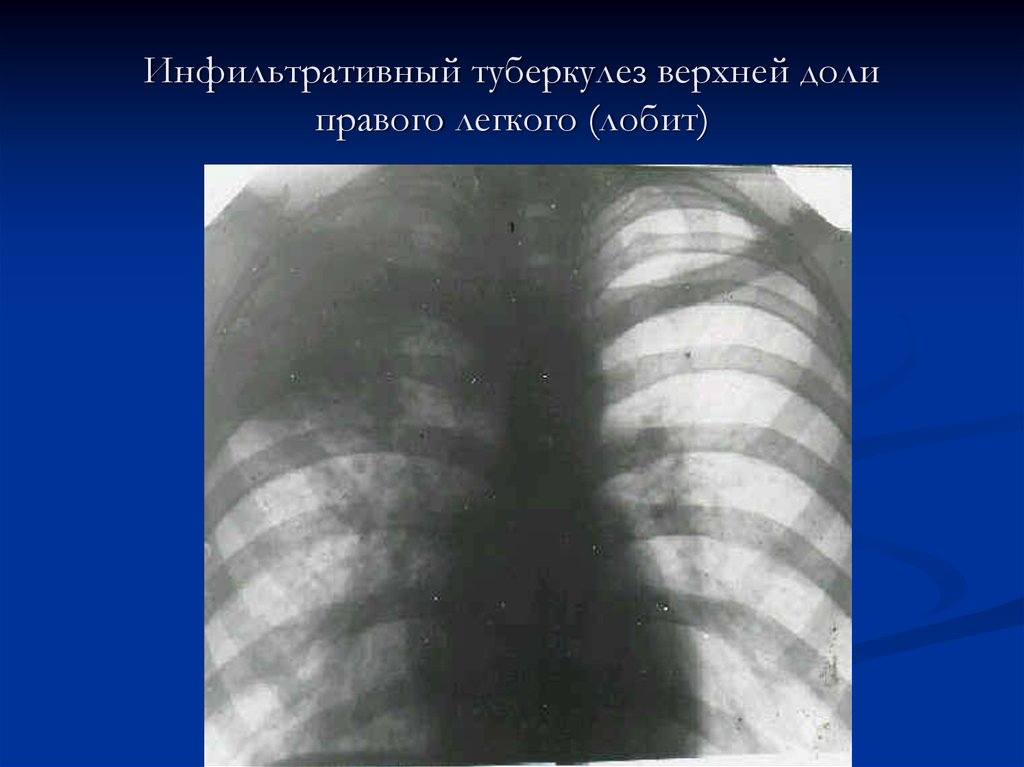

Очаговый и инфильтративный туберкулез презентация - 94 фото